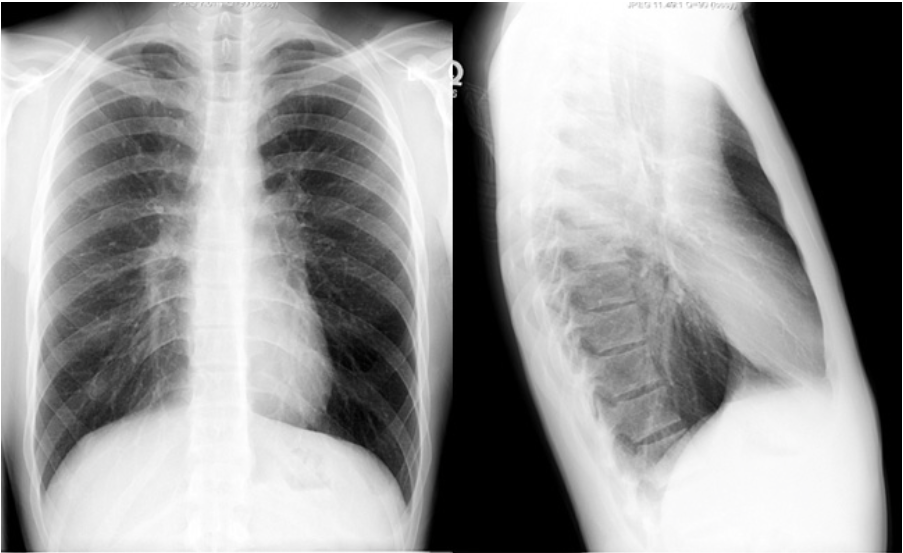

What will COPD show on CXR?

Hyperinflation

It will be associated with blebs and paucity of vascular markings in the outer third of the film. These are zones of avascularity.